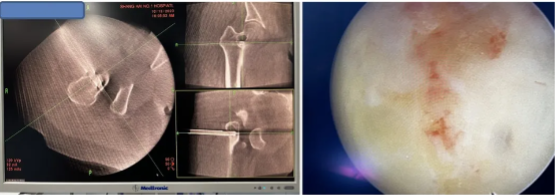

图4: 微创手术配置实时三维CT及最新美敦力S8导航

图6:导航下一次穿刺到病灶,病灶磨钻清理,孔镜通道下可视化操作